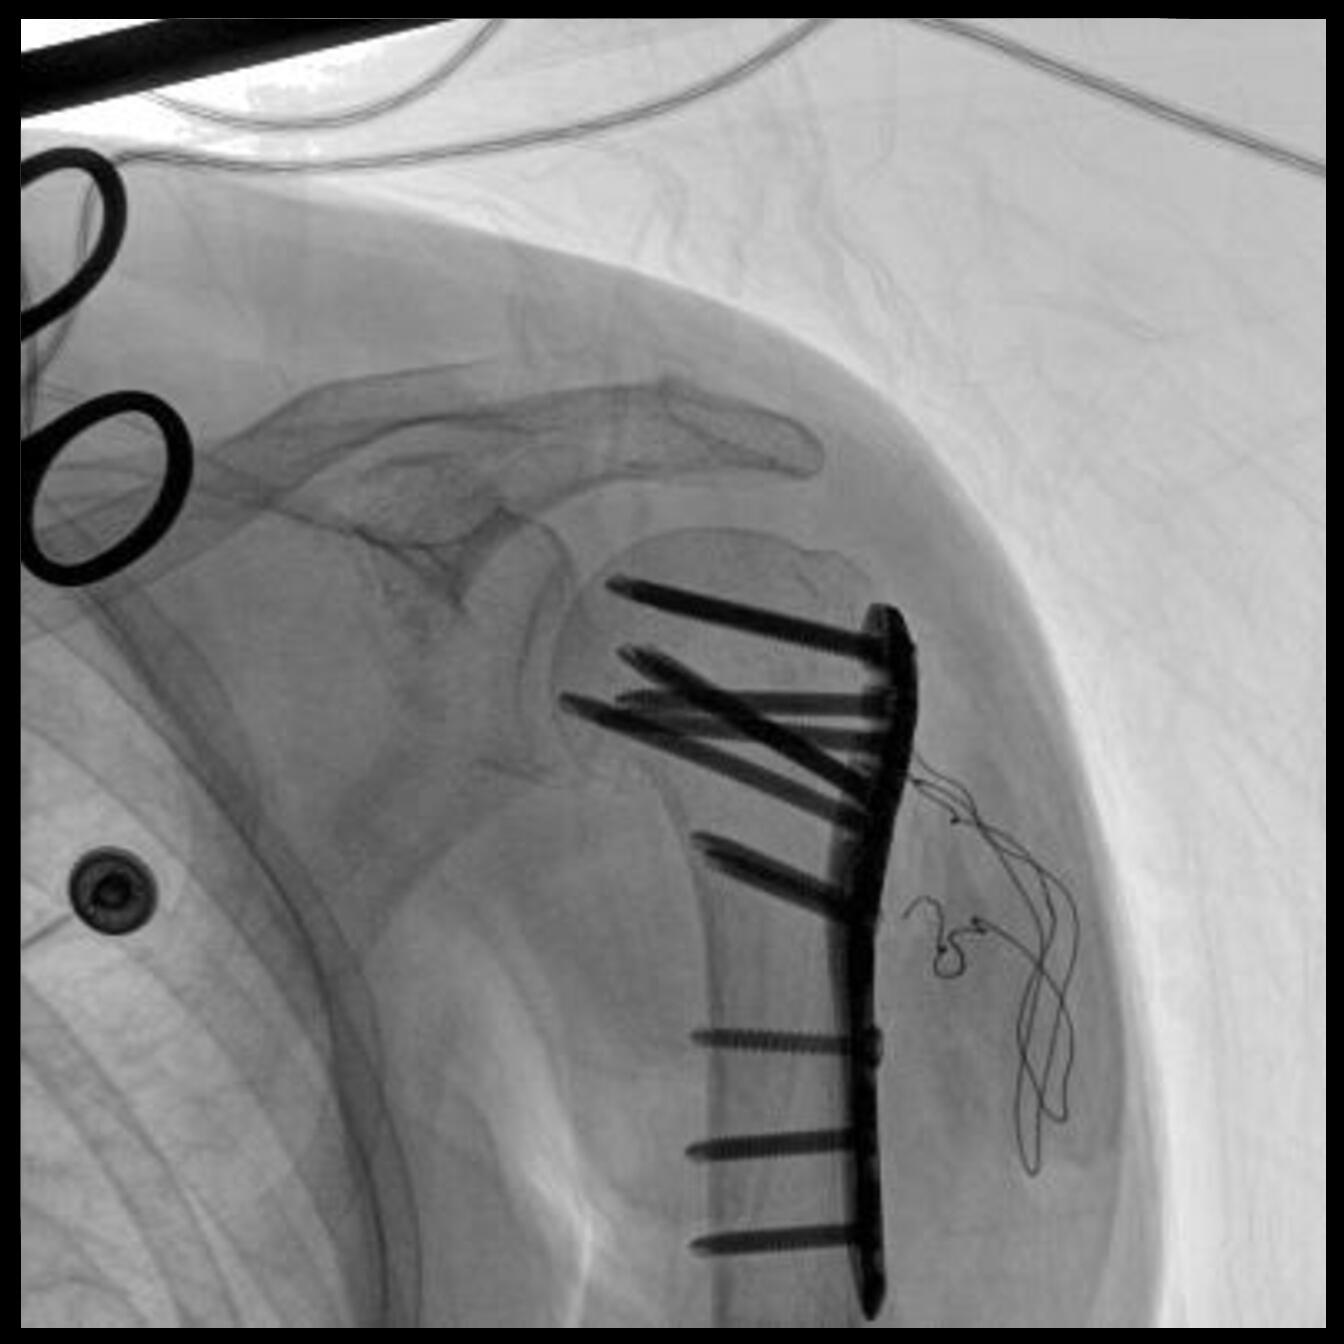

PLX118F-Plus配備了兩種平板尺寸,大尺寸動(dòng)態(tài)平板探測(cè)器成像面積較傳統(tǒng)平板探測(cè)器提升了25%以上,在視野需求大的手術(shù)中,便于醫(yī)生更好定位病灶點(diǎn),規(guī)劃手術(shù)方案,減少因視野范圍不足而多次透視、點(diǎn)片造成的不便。